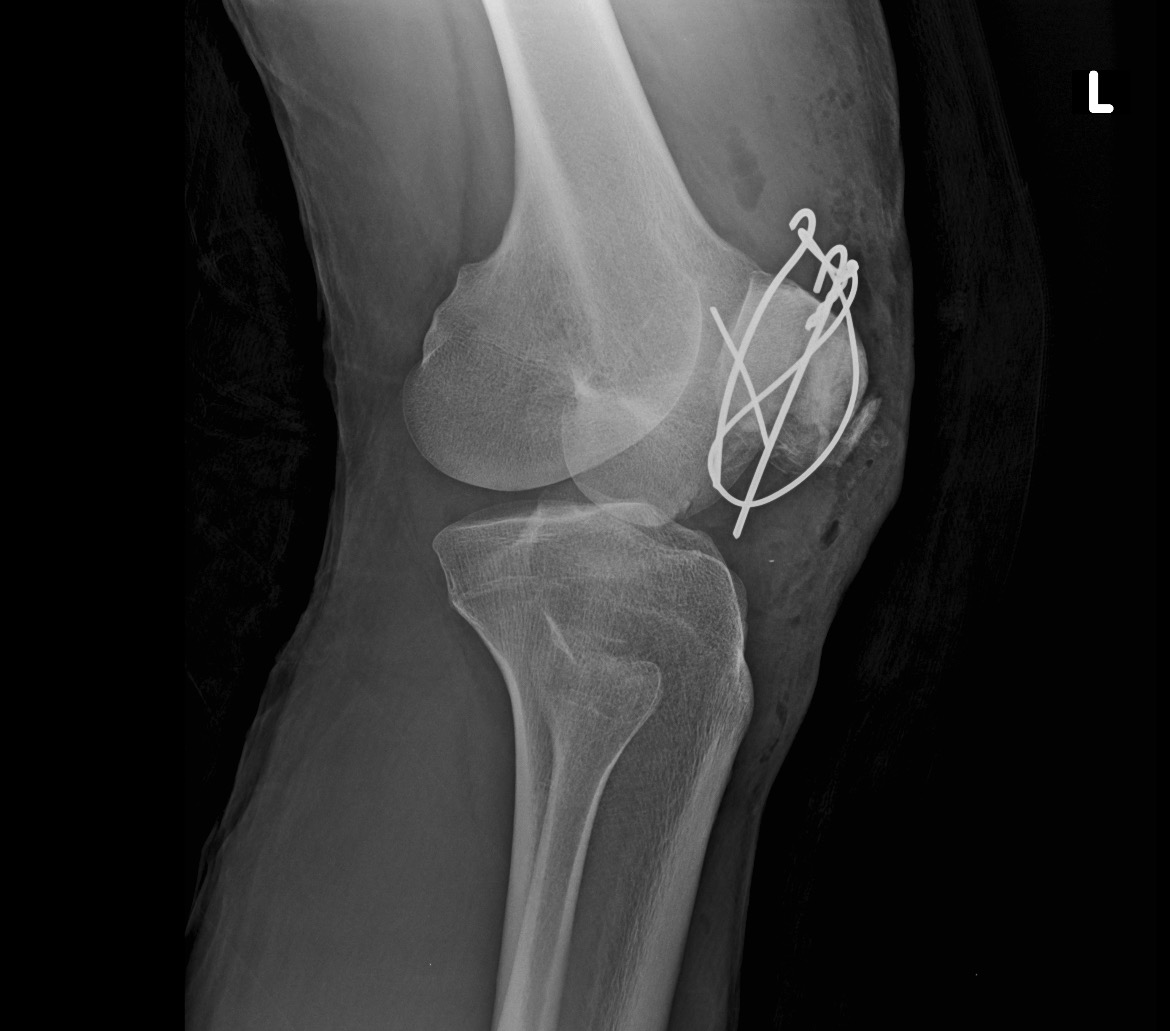

Salí del quirófano con 3 clavos y un alambre para unir los pedazos de mi rótula, muchos puntos y mucho dolor.